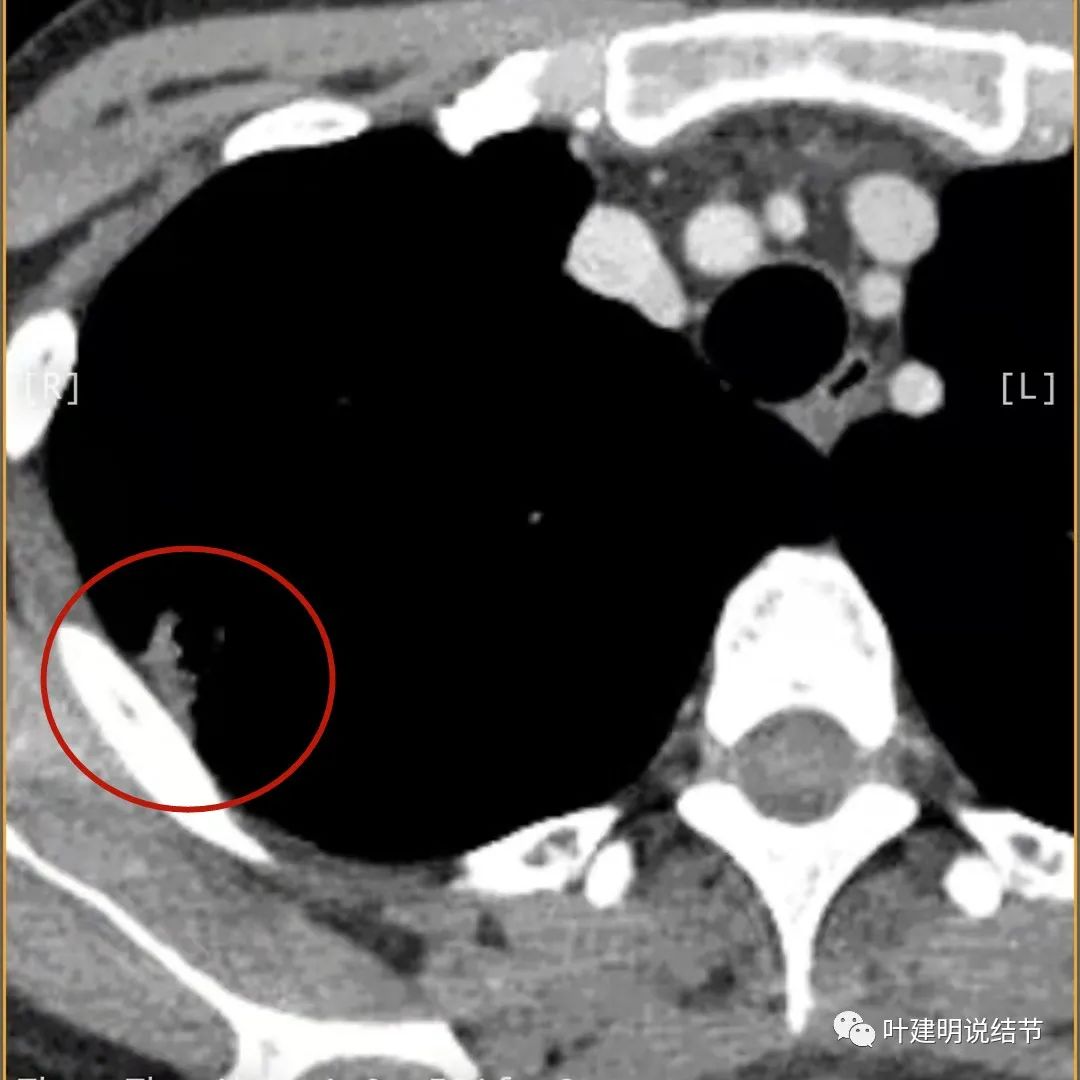

上图病灶的边相对比较光,没有毛刺征,邻近胸膜增厚

上图病灶边缘比较平直,没有膨胀性(桔色箭头),旁边的磨玻璃影淡且界限不清,邻近胸膜增厚。